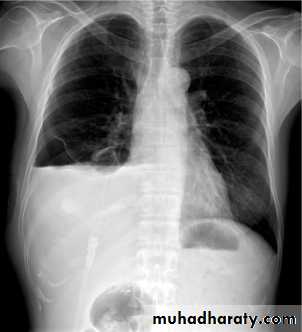

Emphysema

47.Emphyzema